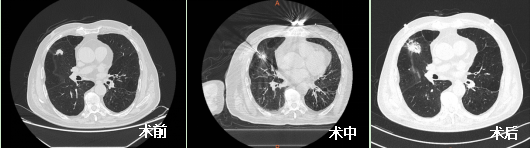

近日,我院呼吸介入团队为一例叶间裂旁肺结节患者进行了微波消融治疗,术中消融针精准命中靶病灶,术后晕征较好地覆盖病灶,恢复良好,术后三天患者好转办理出院。

为进一步进行治疗,王开金副主任带领胡学进副主任医师、陈进主治医师等呼吸介入团队联合麻醉科王艳冰副主任进行了缜密的术前讨论,综合评估患者的整体状况,术前讨论决定为患者右肺上叶高危结节进行微波消融术。做好充分术前准备后,团队于6月16日CT引导下行右肺上叶结节微波消融术,术程顺利,全程无痛,术后无并发症出现。现患者愈后良好,于术后第三天办理出院,并拟1月后对右肺中叶结节行氩氦刀冷冻消融术。

刘爷爷符合专家共识推荐的第一、四条,但他的肺结节紧邻叶间裂,极易出现气胸及支气管胸膜瘘,经过我院呼吸介入团队认真的术前准备、精准的术中布针,较好地完成了手术。此次微波消融术的成功开展,标志着呼吸与危重症医学科微创治疗技术再上新台阶。为患者身心健康和生命安全保驾护航,重庆医科大学附属璧山医院呼吸与危重症医学科一直在努力!